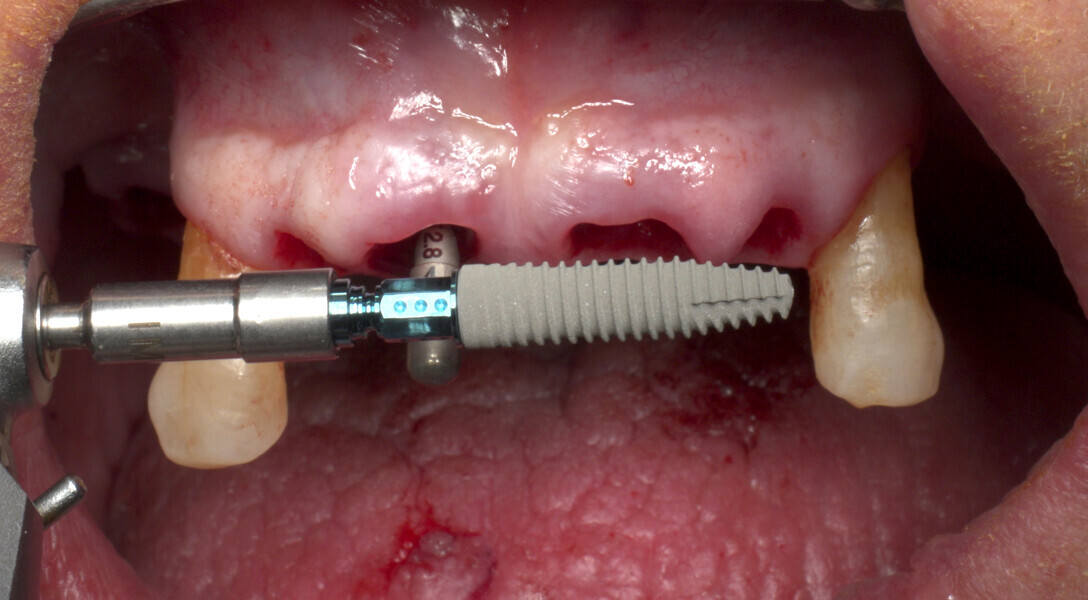

The fully digital Pro Arch protocol